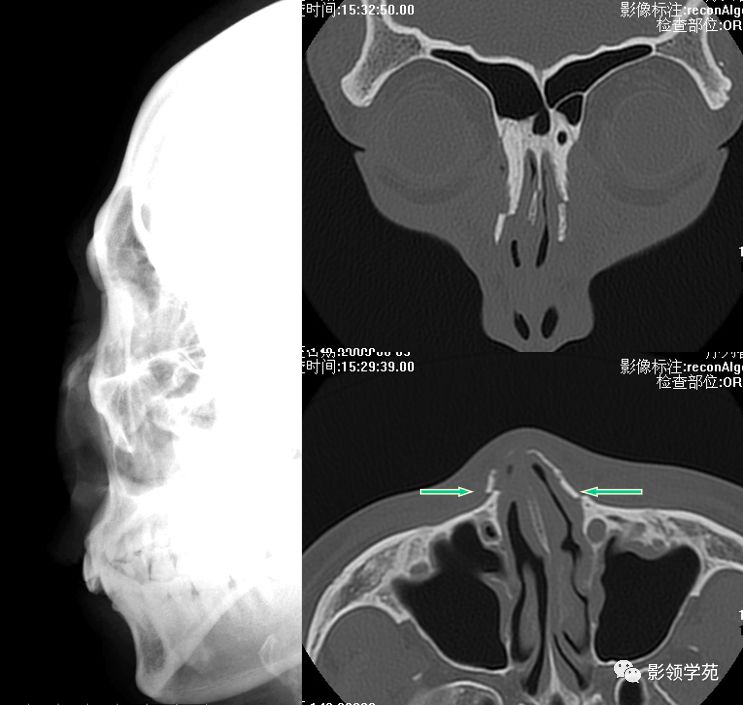

双侧鼻骨骨折

鼻中隔骨折